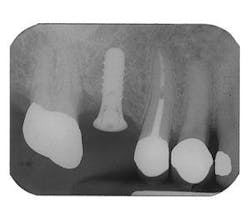

Figure 9 - ITI implant placement Tooth No. 3

Figure 10 - Restored implants